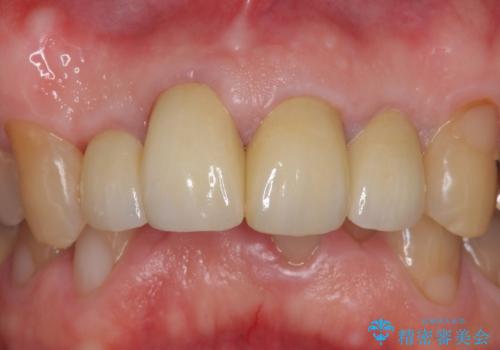

- 前歯の見た目が気になるといらっしゃった方の症例です。

再根管治療後、オールセラミッククラウンによる補綴を行いました。

今回用いたオールセラミッククラウンは、ジルコニアフレームという白い素材の上にセラミックを盛っているため審美性が非常に高いのが特徴です。

またジルコニアは人工ダイヤモンドの材料にも使われているほど高い強度を持っており、そのためオールセラミッククラウンは審美性だけでなく、奥歯やブリッジの補綴も可能とするクラウンです。